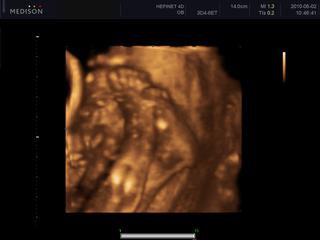

ahojte.krakulka...zatial sem patrim podla pozitivnych testov.v pondelok idem na sono tak hadam budem mudrejsia a zubrienka je tam kde ma byt a neusalasila sa niekde vo vajickovode.

chodim aj nechodim do Piestan....podla potreby.naposledy som sa rozhodla pre IUI.je tam nove centrum cca od agusta minuleho roku.takze su na zaciatku a su straaaasne mili.teda hlavne doktor co tam je.